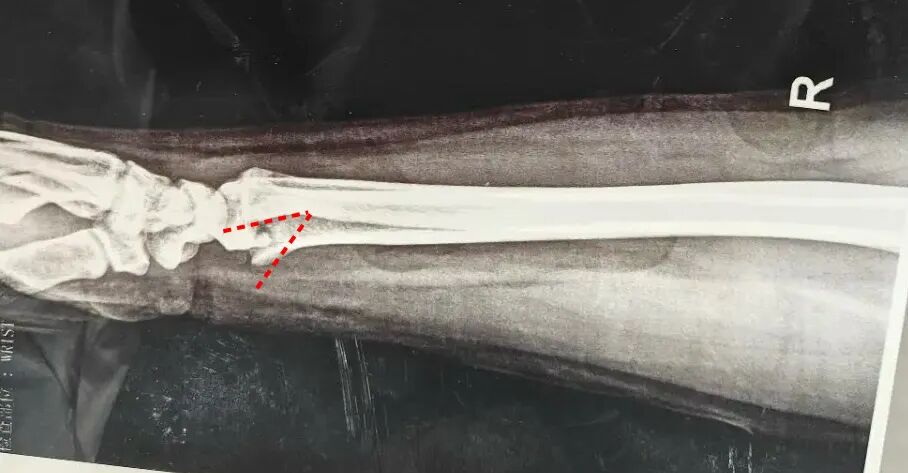

如图:这是一个很常见的复位问题,其主要原因在于骨折端骨折后相互嵌插、在手法复位中只解除了一部分嵌插。

这种相互嵌插的克雷氏骨折最容易造成上述复位后残留掌侧角度的问题。

其根本原因在于,牵引复位中直接掌倾只纠正了背侧嵌插。

如果进一步想纠正掌侧嵌插核心因素有两个:

1.足够的牵引力

2.解除嵌插、适当反折后在掌倾